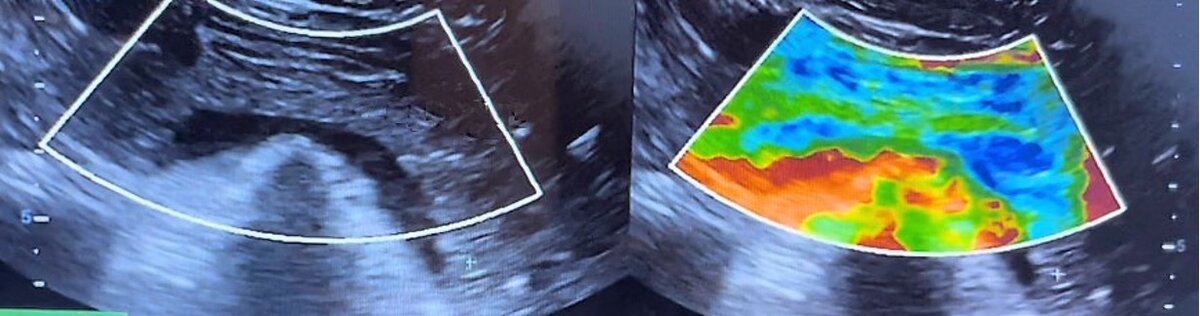

Как проходит само исследование: на первом этапе врач ультразвуковой диагностики находит поджелудочную железу и применяет к ней STE-картирование, при котором самые жесткие участки согласно шкале становятся отличимы от нормальной ткани железы – так как на картинке ниже (железа это похожий на запятую серый вытянутый орган над черной горизонтальной полоской селезеночной вены). Слева обычное УЗ - изображение, справа- с применением картирования. Жесткий очаг в хвосте окрашен синим и голубым цветом.